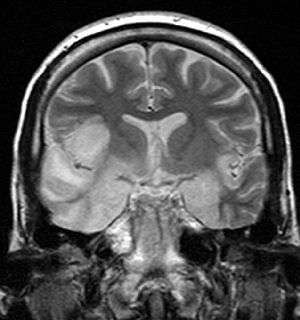

Coronal T2-weighted MR image shows high signal in the temporal lobes including hippocampal formations and parahippocampal gyrae, insulae, and right inferior frontal gyrus. A brain biopsy was performed and the histology was consistent with encephalitis. PCR was repeated on the biopsy specimen and was positive for HSV | |

Limbic encephalitis refers to inflammatory disease confined to the limbic system of the brain. The clinical presentation often includes disorientation, disinhibition, memory loss, seizures, and behavioral anomalies. MRI imaging reveals T2 hyperintensity in the structures of the medial temporal lobes, and in some cases, other limbic structures. Some cases of limbic encephalitis are of autoimmune origin.[12]

- Brain scan, done by MRI, can determine inflammation and differentiate from other possible causes.